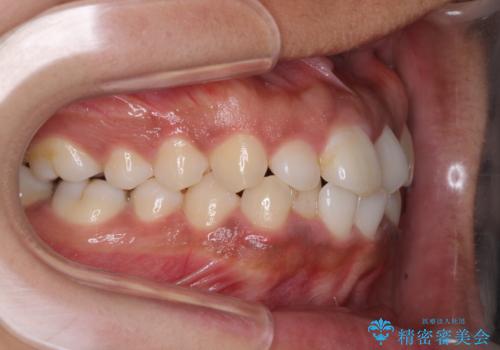

- 上下前歯の叢生を気にして来院された患者様です。

当初はインビザラインにて治療を開始しましたが、自己管理による治療が難しくなり、ワイヤー矯正へ転換して継続しました。